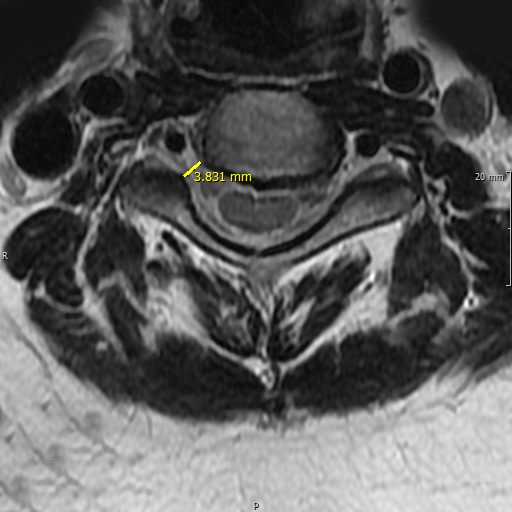

• 경추후종인대골화증 진단

후종인대골화증이 의심될때는 MRI검사를 시행하여 정확히 판단하는 것이 필요합니다.

후종인대골화증은 골변성을 동반하기 때문에 단순 X-ray를 통해 발견할 순 있지만

골화된 종괴의 모양과 크기, 척추관 협착과 압박 정도, 척수의 신경 변성 유무 등을 정밀하게 파악하기 위해서는 CT 또는 MRI를 통해 정확한 평가를 받고 치료에 대한 계획을 잡으시는 것이 중요합니다.